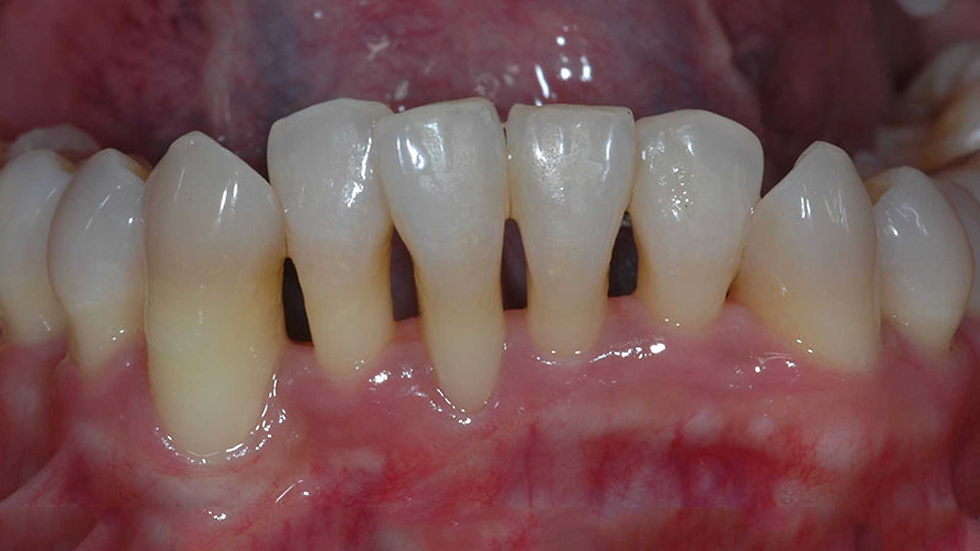

Receding gums, or gingival recession, is a common dental issue that affects many people. It happens when the gum tissue that surrounds and supports the teeth pulls back, exposing the tooth’s root. This can lead to tooth sensitivity, decay, and other dental problems. In this article, we’ll explore the common causes of receding gums, its symptoms, and ways to prevent it.

The symptoms of receding gums may vary, depending on the severity of the issue. Here are some common symptoms to look out for:

Teeth that appear longer than usual.

Gum recession or a notch near the gum line.